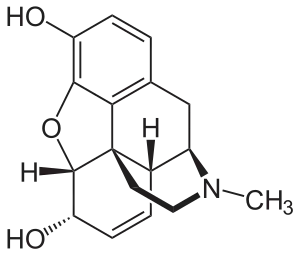

Morphine Morphine |

Morphine family

- 14-Hydroxymorphine [1]

- Desomorphine (dihydrodesoxymorphine)

- Dihydromorphine

Structures of Morphine family

| Morphine family | ||||

|---|---|---|---|---|

Desomorphine Desomorphine (Dihydrodesoxymorphine) |

Dihydromorphine Dihydromorphine |